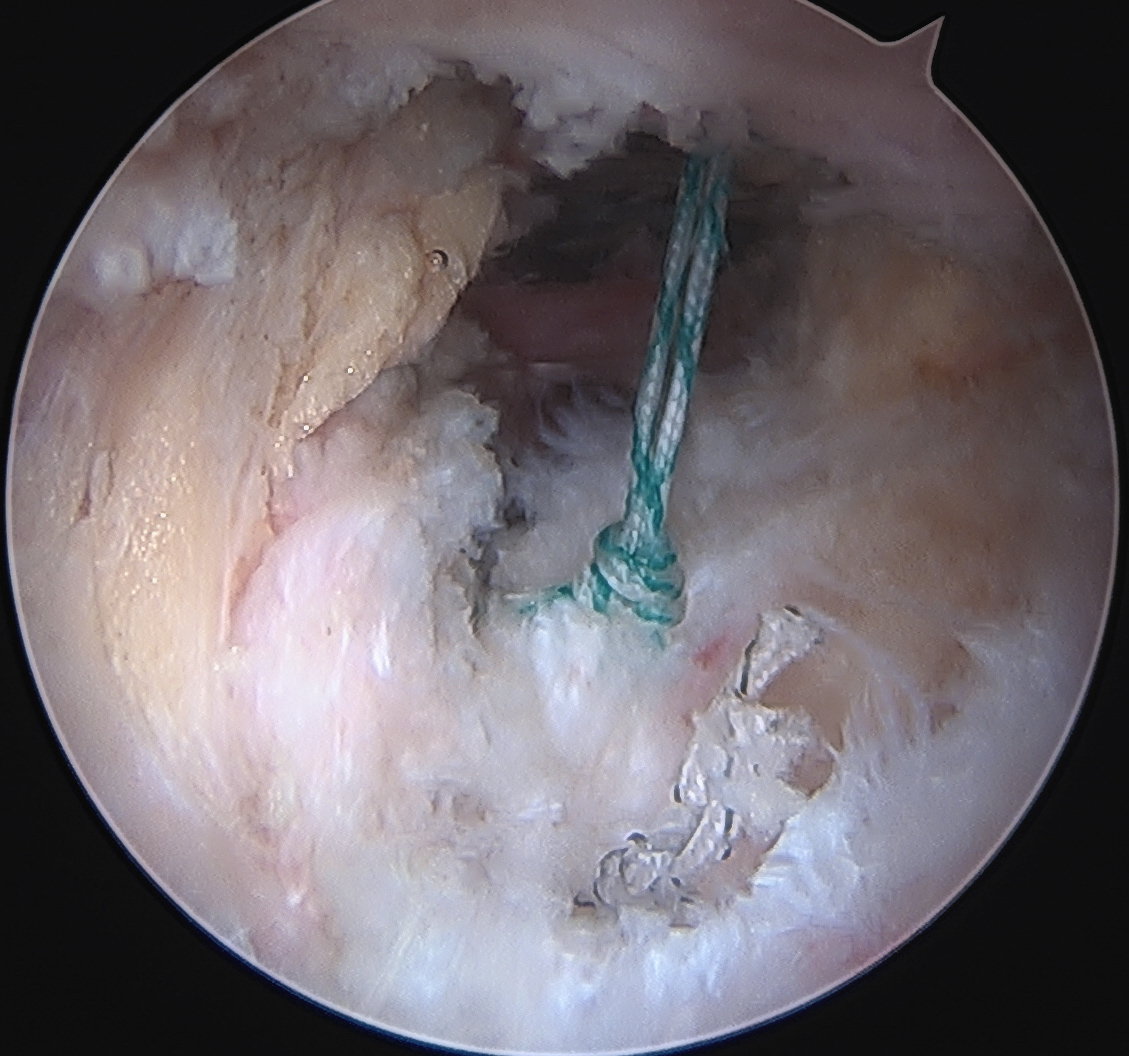

Labral repair

Options

- knotted versus knotless anchors

- straight versus curved

Must avoid intra-articular penetration